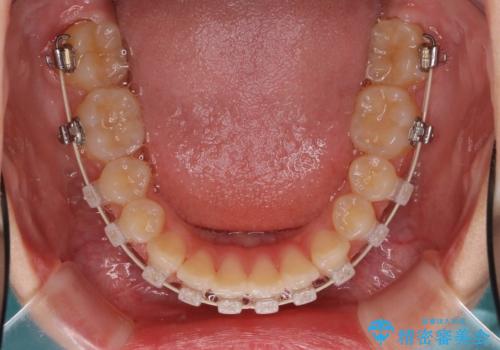

- 矯正装置

- ハーフリンガル

- ハーフリンガルシステムによる矯正治療を行いながら、スペースコントロールをみて前歯を仮歯へ

→矯正の終了をメドに仮歯をセラミックへ置き換える